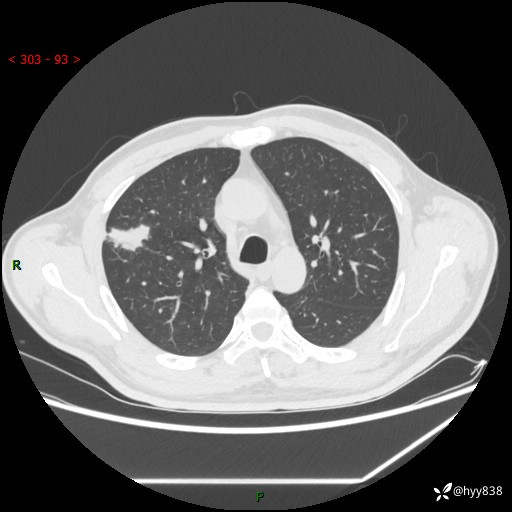

现病史:患者2天前体检完善胸部CT提示:右上肺团块影,炎症可能,肿瘤性病变不除外,冠状动脉钙化,无咳嗽、咳痰,无寒战发热,无恶心、呕吐等其他特殊不适,未予以特殊治疗,现为明确病变性质来我院就诊,门诊以“肺肿物性质待查”收入我科。 起病以来,患者精神、饮食、睡眠可,大小便正常,体力体重较前无明显变化。

胸部CT平扫+增强